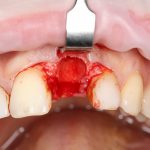

Рекомендации по установке имплантов. Для всех. Часть V.